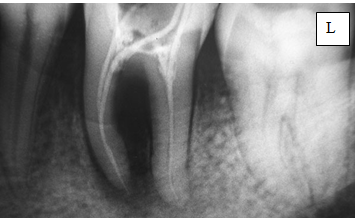

4. название – внутриротовая рентгенограмма зуба 3.6

По снимку всё понятно основное, самое главное: деструкция костной ткани в области бифуркации корней и в области медиального корня, а также расширение период.щели